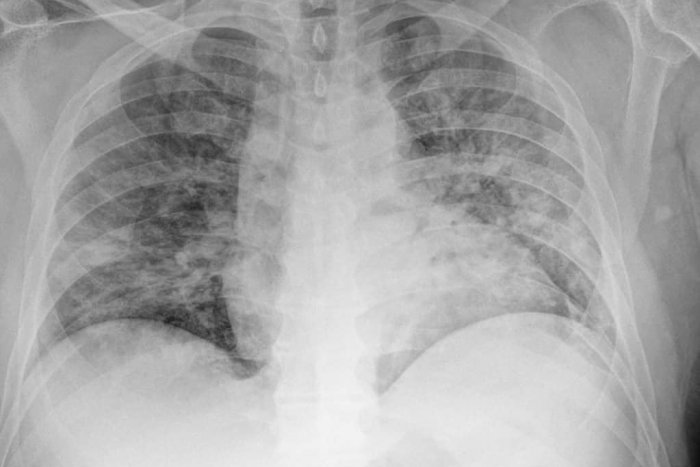

Primár sa vyjadril aj k tomu, koľko pacientov má v sebe vakcíny. „K dnešnému dňu máme na covid oddelení 10 pacientov, z nich 9 neočkovaných. V porovnaní s druhou vlnou sú to mladšie ročníky. Poslední prijatí sú čerství päťdesiatnici s ťažkým obojstranným zápalom pľúc. Okamžite napojení na HFNO (High-flow nasal oxygen), predstupeň umelej pľúcnej ventilácie,“ opísal odborník a dodal aj snímok pľúc pacienta s covidom a neočkovaného.

Snímok ako dôkaz

„Pacient štyri dni po pozitívnom teste, šesť dní od začiatku ťažkostí. V produktívnom veku, pracujúci. Dusiaci sa. Saturácia pri odvoze z domu pod 60 %. Obojstranný zápal pľúc. Nutnosť okamžitej neinvazívnej ventilácie HFNO. Neočkovaný…“ uvádza lekár v statuse na Facebooku.